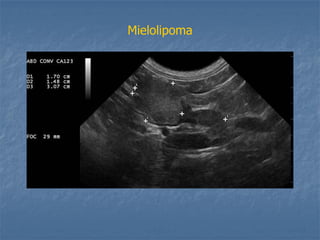

Mielolipoma